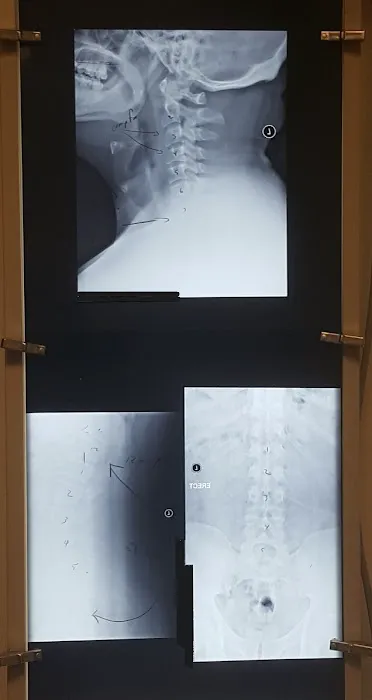

Jun 08, 2023 · Dennis WhippleSimply put- Dr. Pat Selimo is absolutely amazing! Dr. Pat is approachable, trust-worthy, knowledgeable, and precise. He always makes himself available when I have a question or need to schedule an appointment last minute. Starting day one- after his free consultation and having some x-rays taken; Dr. Pat and I reviewed the results from my examination & discussed the course of action that he believed would be best in alleviating the nagging pain I was experiencing in my knees, hips, and neck. I've been seeing Dr. Pat for three months now and the results have been astonishing! The pain is virtually gone and because of this, my quality of life has drastically improved. I cannot thank Dr. Pat enough!What I like most about Dr. Pat is that he is trust-worthy and personable.I had visited a ton of chiropractors before I met Dr. Pat, and none of them compare. More importantly than anything else, he truly cares about his patients. My experience has been nothing short of amazing and I highly recommend his services to anybody & everybody who is looking for a chiropractor! Dr. Pat Selimo is the best!